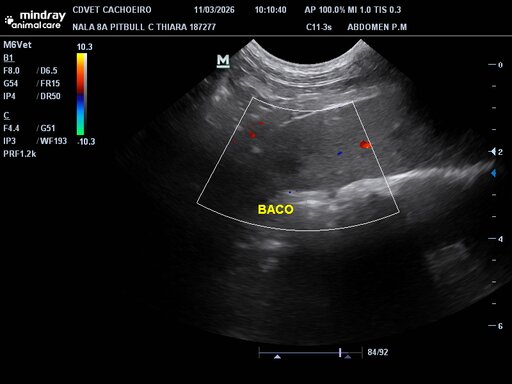

Olá pessoal do bem! Minha cadela Nala precisará passar por uma cirurgia para retirada de uma estrutura nodular no baço e precisaremos da ajuda de todos nesse momento! Desde já agradeço a quem puder e quiser nos ajudar!